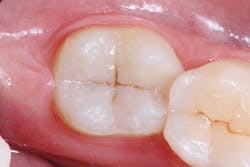

After adhesive treatment, Tetric EvoFlow Bulk Fill (IVA shade, Ivoclar Vivadent) was injected on the pulpal floor of the cavity in an increment of 4 mm, leaving the thickness for packable resin composite approximately 1.2 mm from the cavosurface margin to allow for final sculpture of the occlusal surface per the manufacturer’s recommendation. After light polymerization, the dentin-like opacity of Tetric EvoFlow Bulk Fill was observed, which masked the dark stump shade and improved esthetics. (figures 4 and 5).